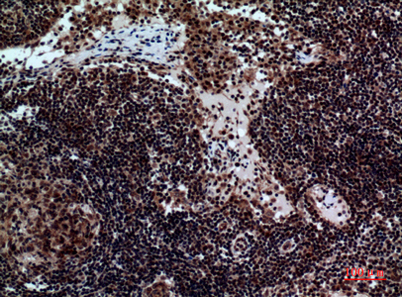

Product name: NKp44 rabbit pAb

Dilutions: Western Blot: 1/500 - 1/2000. IHC-p: 1/100-1/300. ELISA: 1/20000. Not yet tested in other applications.

Immunogen: The antiserum was produced against synthesized peptide derived from the Internal region of human NCR2. AA range:61-110